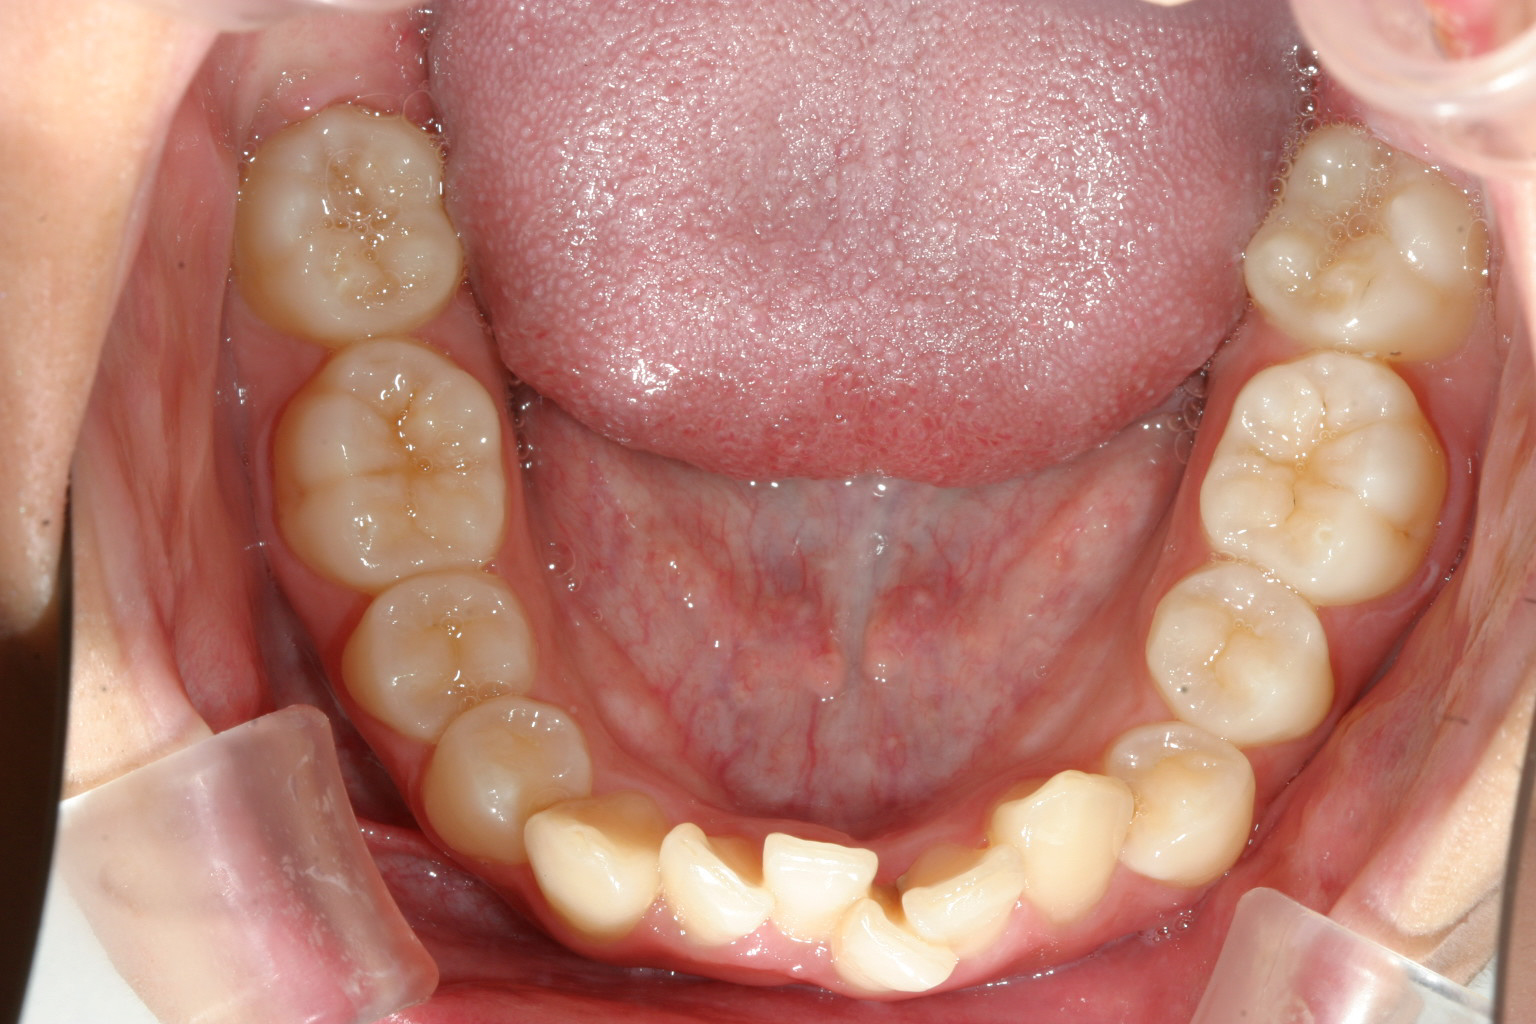

上の前歯に押されたせいで下の前歯がガタガタになっています。

上を先に出して下の前歯も綺麗に並べました。

綺麗なオーバーバイトに改善しました。